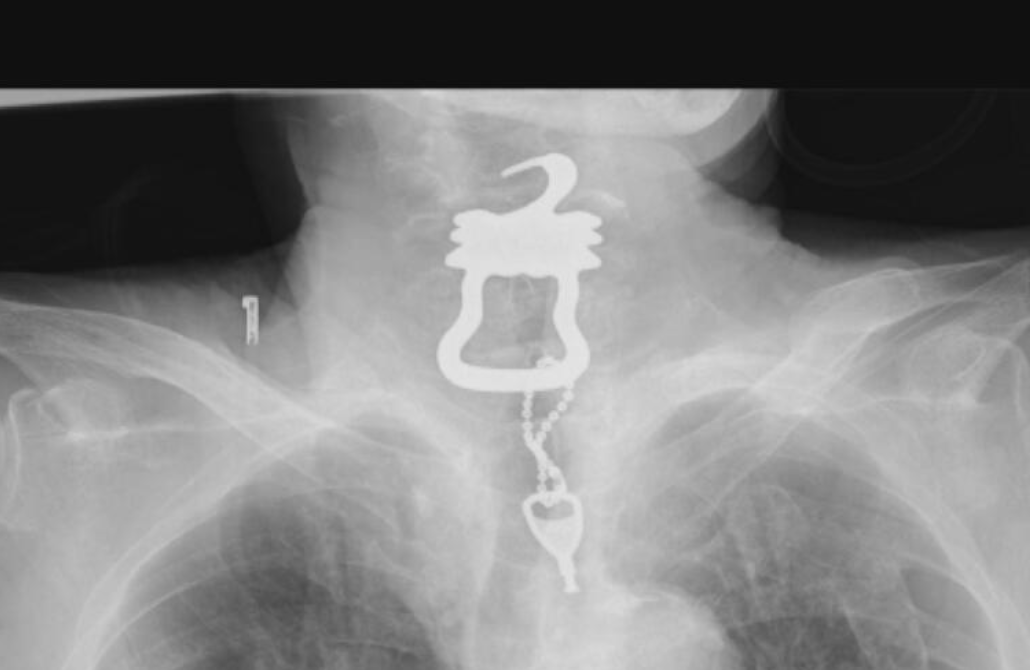

根據《讀賣電視台》報導,死者大西健一2022年1月因跌倒導致胸骨骨折而入院,原本持續住院接受復健。然而他9月卻向醫師表示喉嚨疼痛,並被確診感染新冠肺炎。但是醫院拍攝X光時卻意外發現喉嚨裡卡著一把鑰匙,而鑰匙上還掛著鑰匙圈,雖然緊急將其取出,但老翁仍於數日後病逝。